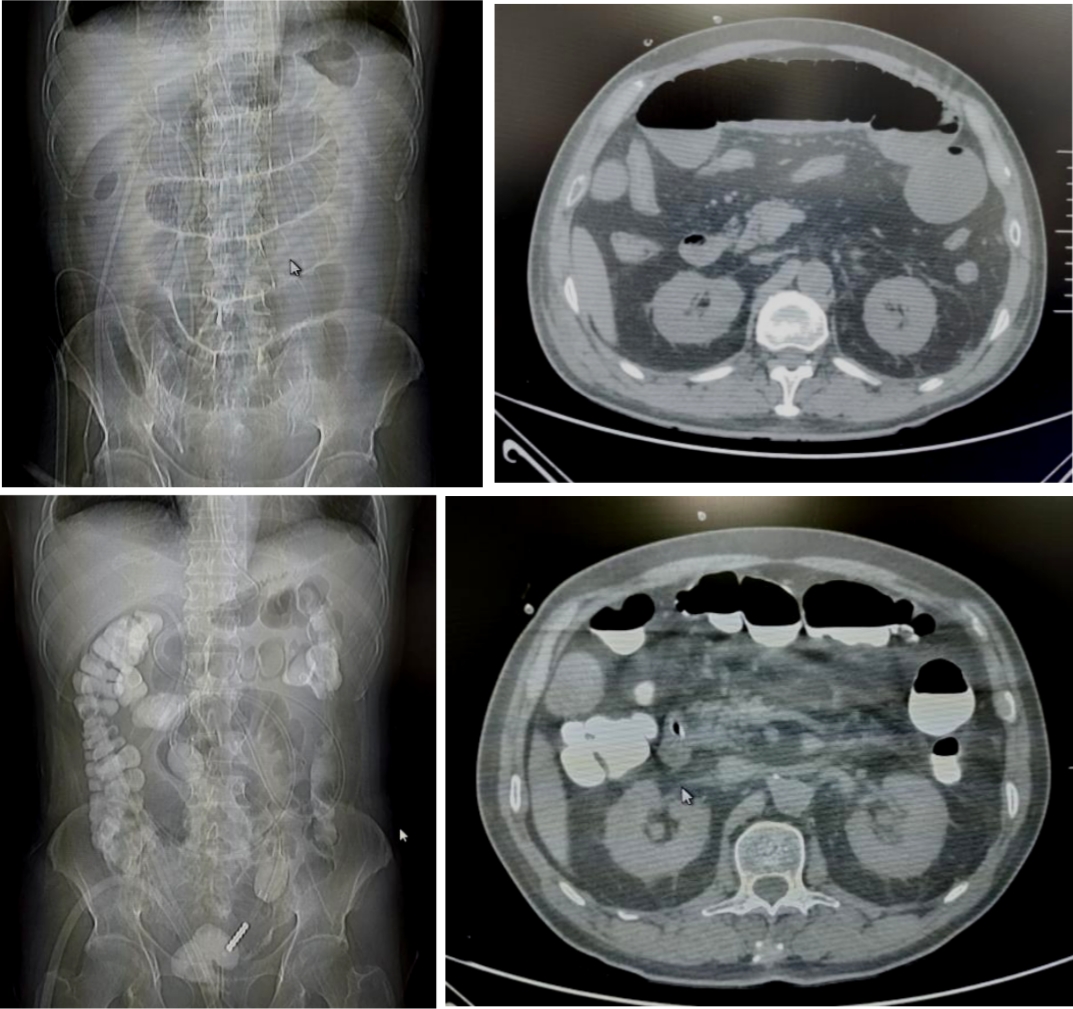

病例1

71岁的患者刘先生,因行膀胱癌根治术、回肠代膀胱术出现肠梗阻。后在我院放射介入室行DSA引导下经鼻肠梗阻导管置入术,术后当日患者腹胀较前明显缓解,术后第6天患者排气、排便,肠管恢复通畅,拔除肠梗阻导管。

病例2

18岁的患者叶女士,因行阑尾穿孔导致盆腔脓肿后出现肠梗阻。后在我院放射介入室行DSA引导下经鼻肠梗阻导管置入术,术后当日患者腹胀较前明显缓解,术后第3天患者排气、排便,肠管恢复通畅,拔除肠梗阻导管。